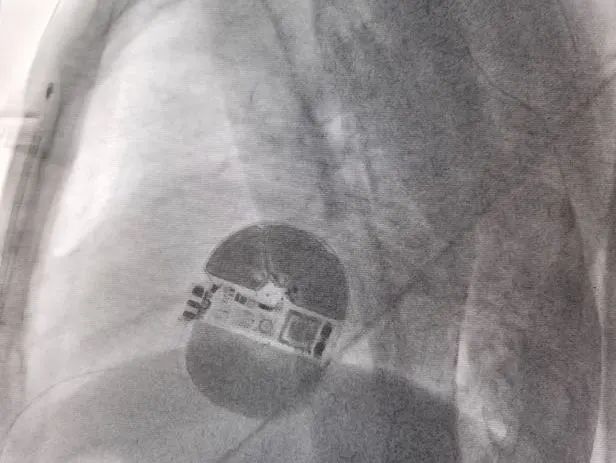

女性患者除颤测试

术中DFT测试

男性患者除颤测试